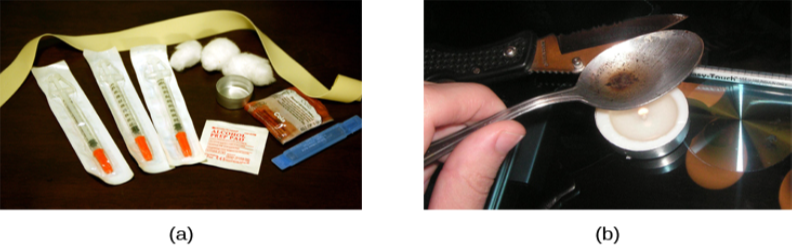

Historically, heroin has been a major opioid drug of abuse (Figure 4.17). Heroin can be snorted, smoked, or injected intravenously. Heroin produces intense feelings of euphoria and pleasure, which are amplified when the heroin is injected intravenously. Following the initial “rush,” users experience 4–6 hours of “going on the nod,” alternating between conscious and semiconscious states. Heroin users often shoot the drug directly into their veins. Some people who have injected many times into their arms will show “track marks,” while other users will inject into areas between their fingers or between their toes, so as not to show obvious track marks and, like all abusers of intravenous drugs, have an increased risk for contraction of both tuberculosis and HIV.

A hallucinogen is one of a class of drugs that results in profound alterations in sensory and perceptual experiences (Figure 4.18). In some cases, users experience vivid visual hallucinations. It is also common for these types of drugs to cause hallucinations of body sensations (e.g., feeling as if you are a giant) and a skewed perception of the passage of time.